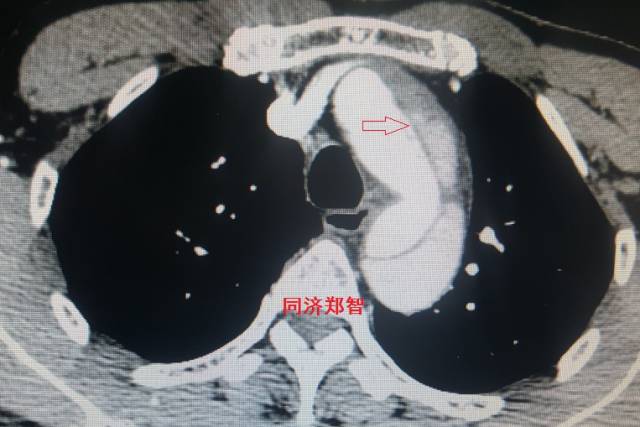

病例五

平扫CT提示主动脉弓层面及右肺动脉层面均可见主动脉血管腔内的内膜片影(红色箭头所示),CTA显示为A型主动脉夹层。